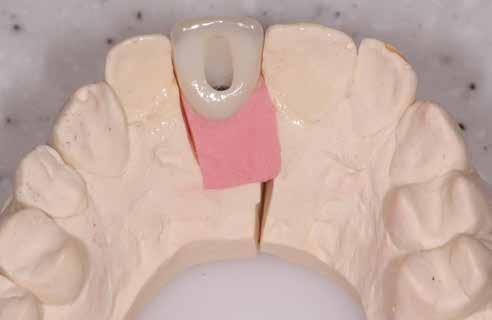

bukkális 1. kép: Kiindulási állapot, 2020. január. 3. kép: Kiindulási CBCT felvétel. 2. kép: Kiindulási állapot a palatinális oldal felől.

6. kép: Implantátum-ágy preparáció. 7. a–b. képek: Implantátum behelyezés. 8. kép: A behelyezett implantátum. 10. a–b képek: Azonnali ideiglenes korona készítése. 9. kép: Megfelelő primer stabilitás.

A 2020 januárjában elkezdett kezeléssorozat befejezését az év márciusában, hazánkba is begyűrűző Covid-19 pandémia késleltette, így kb. 6 hónap gyógyulás után láttunk hozzá az emergencia profil és a gingivális zenit ideiglenes koronával történő formázásához (11. és 12. kép). A 3 hetente végzett apró alakításokkal sikerült megfelelő ínyprofilt kialakítani, a „rózsaszín esztétika” a páciens számára is megfelelő volt. A bal felső nagymetsző fog meziális kompozit tömés cseréjét követően, individualizált nyitott kanalas lenyomati fejet készítettünk: az akrilát ideiglenes korona profilját átlátszó szilikonnal lemásoltuk, majd a körszimmetrikus gyári lenyomati fej és az ideiglenes korona kontúrja közötti hézagot folyékony kompozittal töltöttük ki (13. kép). Az így készített egyéni lenyomati fejjel vettünk lenyomatot a végleges, kerámialeplezésű cirkónium-dioxid vázas, átmenő csavaros rögzítésű koronához. (A fogtechnikai munkát Nébl Péter fogtechnikusmester készítette.), (14., 15., 16 és 17. képek).

13. a–c képek: Egyéni lenyomati fej készítése. 13. d kép: Egyéni lenyomati fej. 15. kép: Cirkónium-dioxid vázpróba, in situ. 14. kép: Kétfázisú, egyidejű nyitott kanalas lenyomat (Aquasil Ultra+ - Dentsply Sirona). 16. a–b képek: A kész munka gipszmintán.